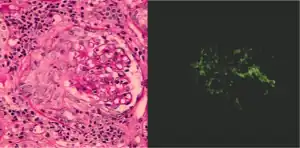

Como ya se dijo, la glomerulonefritis puede tener una patogenia inmune o inflamatoria y aunque en algunas situaciones es posible establecer un diagnóstico específico sobre la base de la presentación clínica y las pruebas de laboratorio, en la mayor parte de los casos es útil realizar una biopsia renal tanto para efectuar la clasificación como para determinar el pronóstico. Además, lo ideal es que las muestras de biopsia se examinen con el microscopio óptico, mediante inmunofluorescencia y por microscopia electrónica porque ese enfoque permitirá diagnosticar el patrón histológico. En algunos casos ese patrón se puede comparar con los resultados de otras pruebas de laboratorio para identificar una etiología específica, pero en muchos otros la enfermedad es idiopática. Aun así, como los tratamientos suelen desarrollarse para patrones histológicos específicos, en el manejo actual de estos trastornos se prefiere este enfoque.[7]

La evaluación histopatológica completa de las muestras obtenidas para la biopsia renal requiere el empleo de microscopia óptica y electrónica y el examen con las técnicas de inmunofluorescencia o inmunoperoxidasa para detectar depósitos de complemento e inmunoglobulina.[7]

Técnicas con inmunofluorescencia e inmunoperoxidasa

Para identificar fenómenos reactivos inmunitarios se utilizan inmunofluorescencia indirecta y tinción con inmunoperoxidasa. La tinción se usa para detectar IgG, IgA e IgM, componentes del sistema del complemento (habitualmente C3, C4 y Clq) y fibrina, que suele verse en las semilunas y en los capilares en los trastornos trombóticos (como el síndrome urémico hemolítico y el síndrome antifosfolípidos). Puede haber depósitos inmunes a lo largo de las asas capilares o en el mesangio y es posible que sean continuos (lineales) o discontinuos (granulares).[7]

El mejor método para el diagnóstico de las enfermedades renales de etiología inmunitaria consiste en realizar la biopsia renal y estudiar con microscopia óptica los tejidos teñidos porque de ese modo se podrá anticipar el pronóstico y seleccionar el tratamiento adecuado. Sin embargo, como hay varios mecanismos inmunitarios que pueden provocar cambios morfológicos similares, también resulta útil la microscopia de inmunofluorescencia con anticuerpos específicos marcados con fluoresceína para determinar el tipo y la localización de los compuestos inmunes en el riñón.[17] Además, la biopsia renal es importante porque no solo permite saber dónde se encuentra la lesión histológica o qué mecanismos intervienen sino también el grado de importancia de dicha lesión, un factor fundamental para decidir qué tipo de manejo terapéutico se requiere y en qué momento iniciarlo.[16]